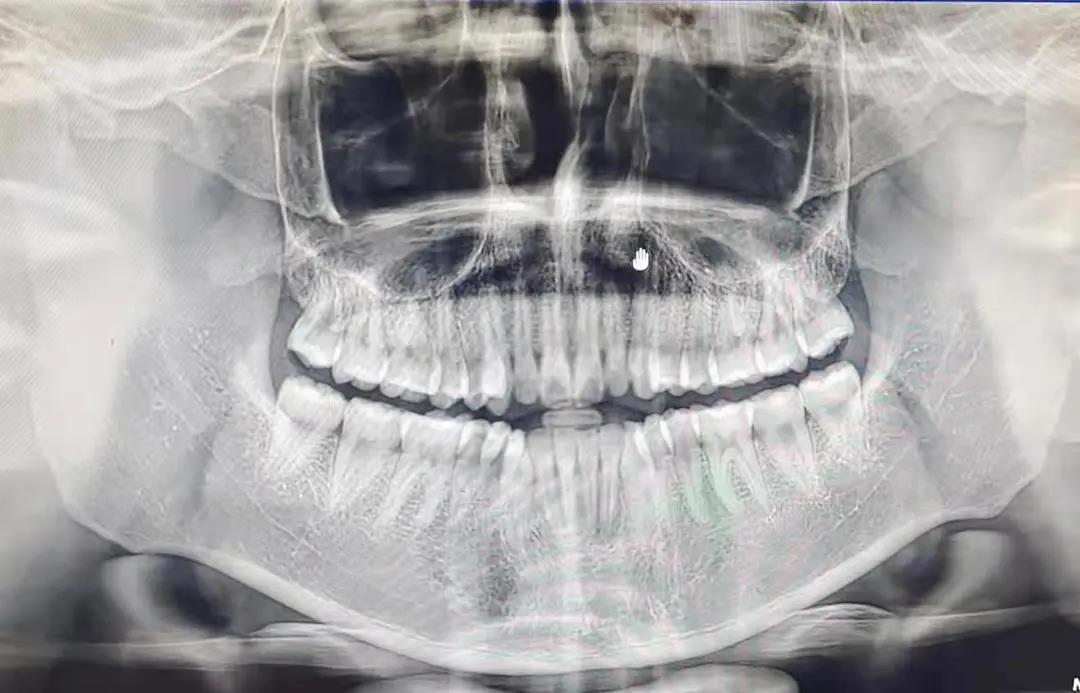

早上八点我们步行前往,到达时,给我们发了口罩、帽子。首先由冯雪老师给我们讲了目前国内外的口腔医学的发展形式,主要包括大学附属医院,口腔医院等。然后参观了院区,之后分组临床见习(正畸,综合,洁牙),正畸其操作精细,震撼,学到了各种操作器的用法和注意事项,然后去了影像室,给我的同学拍了片子,他的牙齿很好,最后进行了感控的基础知识教育,其中印象深刻的是器械的消毒灭菌的流程(回收~分拣~清洗~烘干~注油~打包~消毒~存放),了解到了感控的极其重要性!

这一次次见习,注定会让我一生铭记。第一次以医生的视角进入医院,有着别样的体验,穿上那身白大褂,立马就和平时的感觉不一样了起来。第一次了解控感的知识,第一次近距离围观拔牙且全程有讲解,第一次直面患者,第一次在职工餐厅吃饭,第一次对自己的未来有了如此清晰的触碰。现在的我,什么都不会,什么都不知道,不知道面对病人如何交流,不知道X光片怎么看,不知道怎样打麻药,可是,这些无知并不妨碍我对老师们心生景仰。这次见习之后,我在内心坚定地对自己说:我要成为和他们一样优秀的牙科医生。